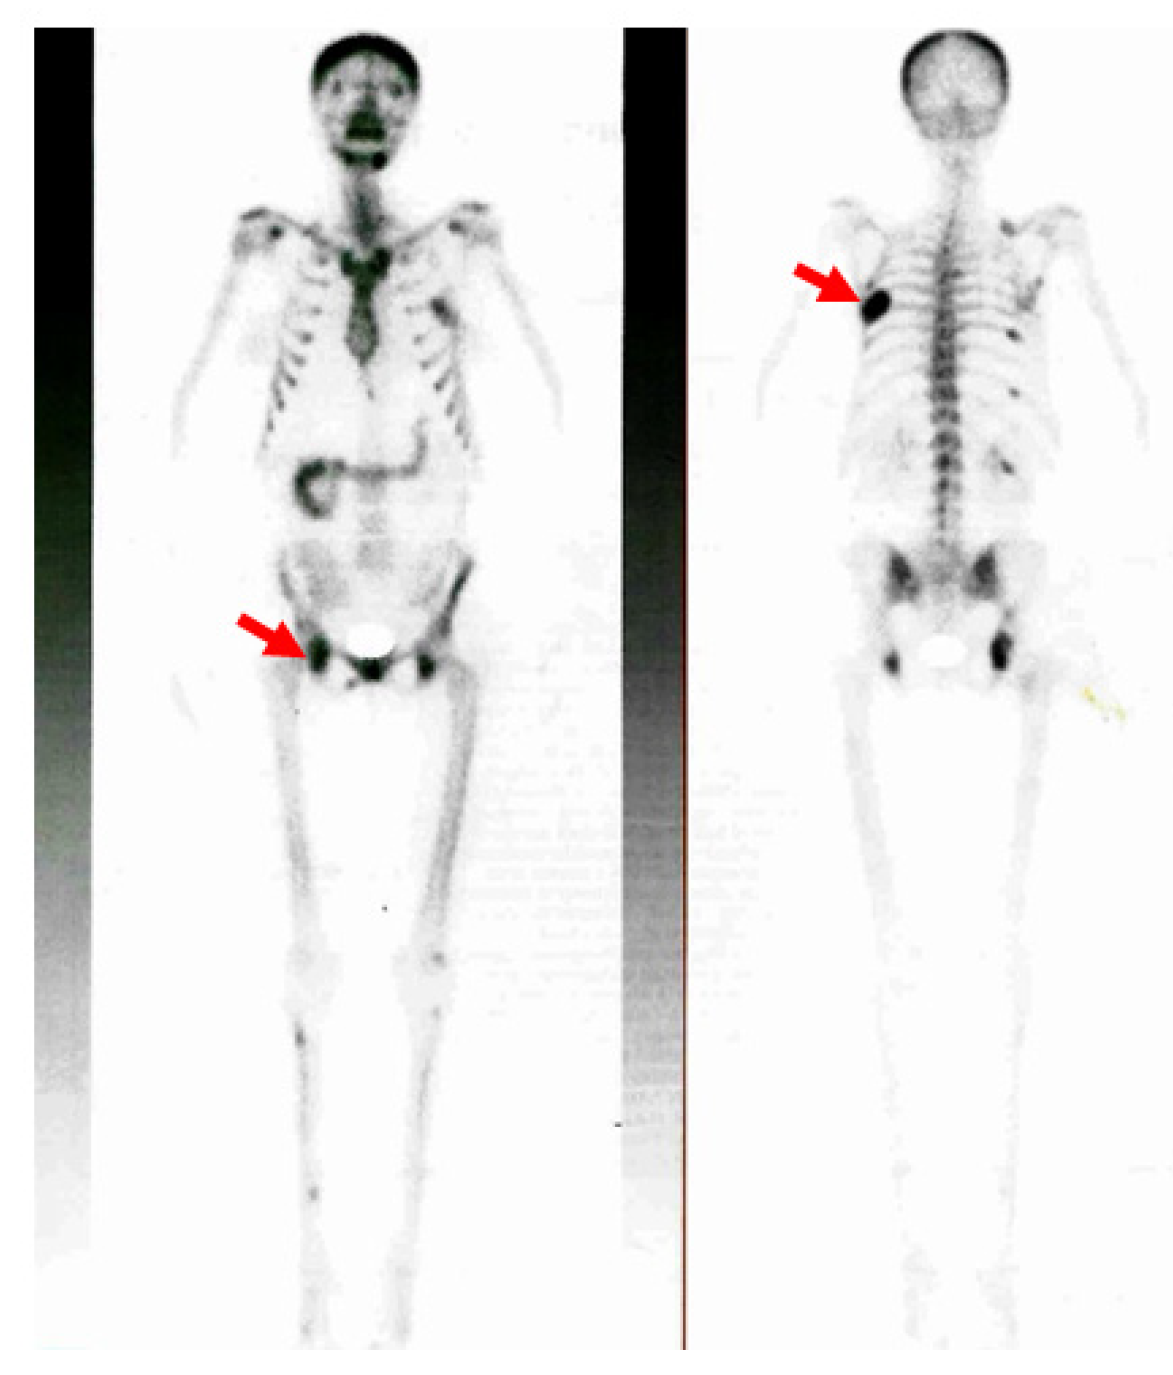

Additionally, the 99m-Tc hydroxymethylene diphosphonate (99mTc-HDP) whole-body bone scintigraphy showed a diffuse increased uptake at the level of the skull and at the local level in the posterior part of the sixth left rib (brown tumor); other mildly increased uptake areas were in the seventh, ninth, and eleventh right posterior ribs, pelvis, and acetabular rim (Figure 7).

Figure 7.

99mTc-HDP whole-body bone scintigraphy: locally increased uptake at the level of the sixth left rib (brown tumor), as well as of the seventh, ninth, and eleventh right posterior ribs, pelvis, and acetabular rim; moderately increased uptake at the scapula-humeral joints and the mandible; diffusely increased uptake at the skull (the red arrows show the brown tumors).